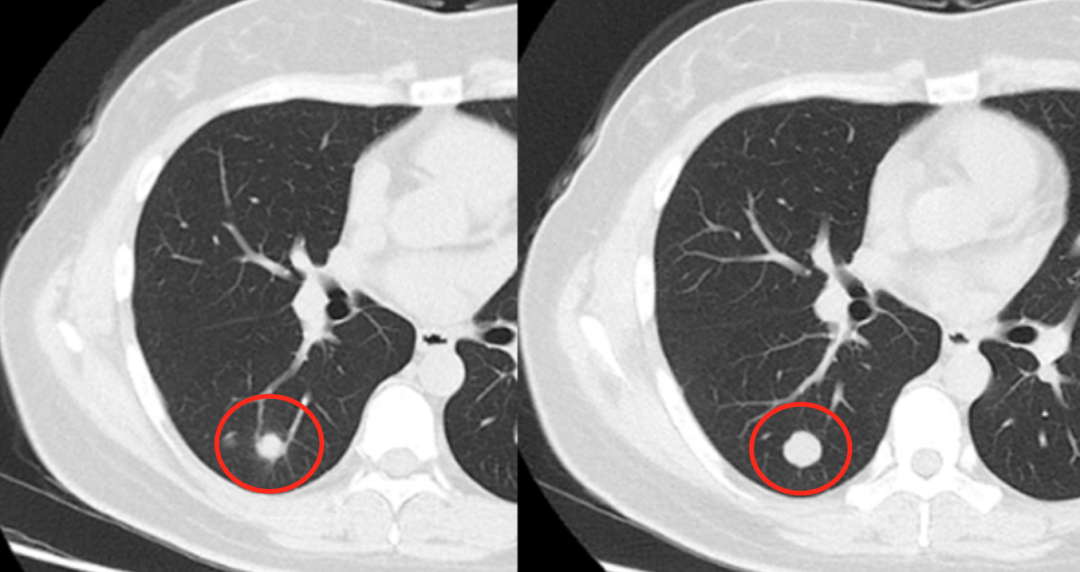

我们再来看上图所示的病灶,刚开始的时候是肺内的一个实性结节,但是边缘并不是很光滑,似乎是有毛刺的。尤其是这个结节经过半年的随诊后,明显增大。对于这种增长的结节,医生很担心它是一个恶性的结节。对于这个患者建议进行手术治疗,但术后的病理是结核。